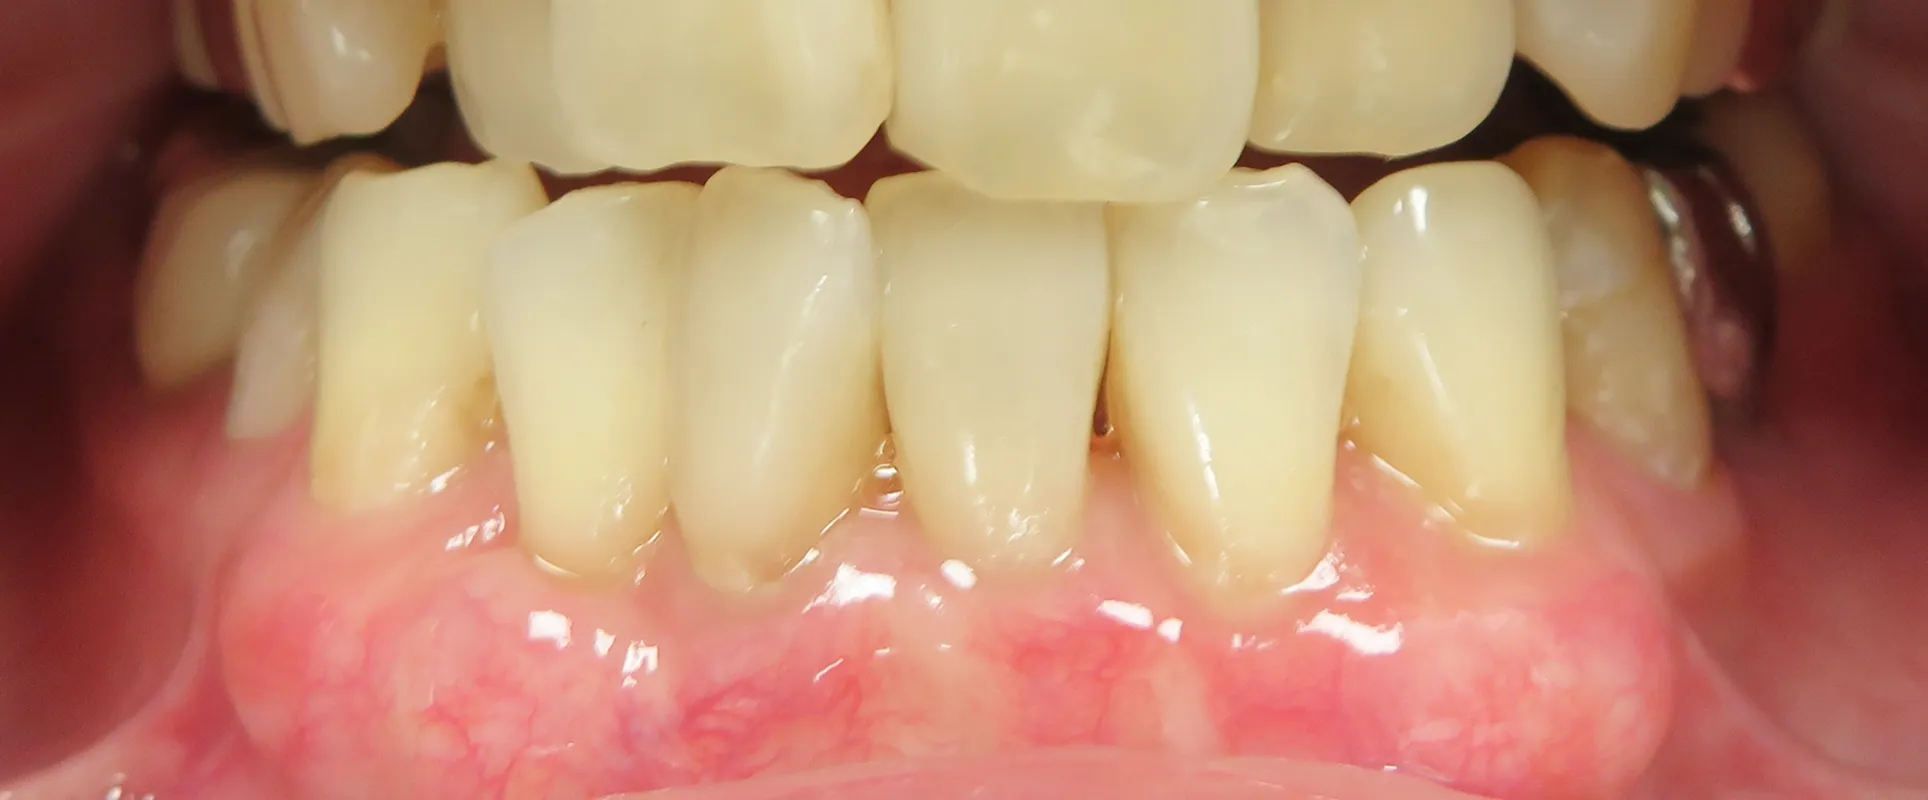

歯肉再生PRP注射の症例写真

BEFORE

AFTER

施術名:PRP注射/料金の目安:上前歯または下前歯 8本 89,000円(税込 97,900円)/施術の副作用リスク:効果の個人差、腫れ、左右差、内出血、ふくらみ、しこり、アレルギー

40代 女性

下前歯(8本)の歯茎に注入

施術前は歯茎が退縮し、歯根が露出している状態で、歯が長く見えていましたが、治療後は歯茎に厚みが増し、歯と歯茎のバランスが改善しました。

あわせて、歯茎の色調も改善し、より自然で若々しい印象となっています。

※効果には個人差があります。